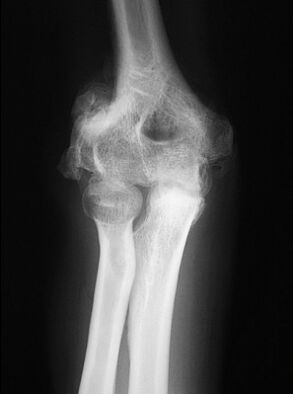

43.一位50歲的T8脊髓損傷患者在3年前受傷之後定期接受物理治療,最近患者開始抱怨膝部附近疼痛,治療師在觸診後發現膝關節附近有紅腫的現象,患者照了一張X光後結果如下圖。患者可能發生了什麼問題? (A)關節攣縮 (B)骨化性關節炎 (C)異位骨化症 (D)痛風 (E)一律給分